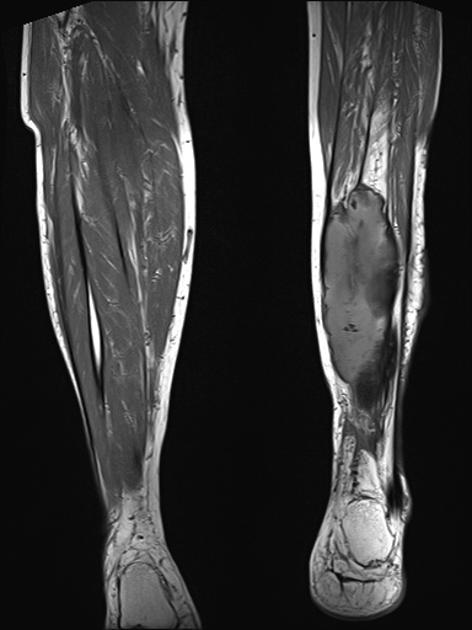

MRI may be used as a means of assessing the extent of the lesion. In the early phase, the lesion is isointense to muscle on the T-1 weighted images and hyperintense to muscle on T-2. As progressive ossification of the periphery occurs in the subacute phase, there will be the formation of a hypointense outer rim on the T-1 weighted images (3). Enhancement is present on the post-contrast images. With further maturation, the lesion becomes hypointense on both the T-1 and T-2 weighted sequences.

Figure 5 is a T-1 weighted image of an MO lesion in the left lower leg. It is fairly isointense to muscle on this image with a low signal periphery. Figure 6 is an accompanying STIR image, which demonstrates a fatty component and thus manifests a uniformly low signal.